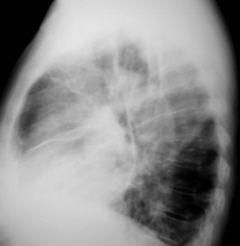

Иллюстрация 2. Фрагмент флюорограммы с увеличением изображения. Пациентка взята «на контроль», произведено дообследование согласно стандарту.